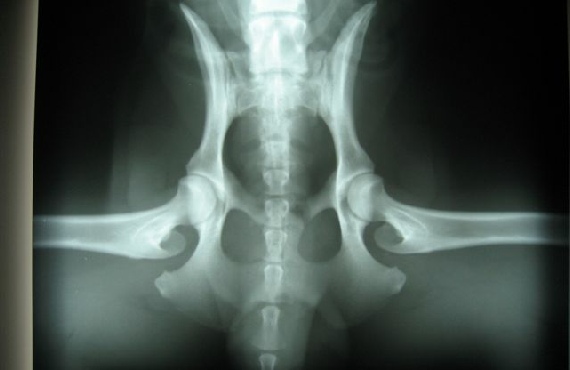

HD / ED RÖNTGENBILDER VON FACE

26.08.08 bekam ich eine Narkose (das fand ich gar nicht toll !!) , aber scheinbar sind diese Röntgenbilder, über meine Hüft- und Ellenbogengelenke, die dann gemacht wurden, ziemlich wichtig.